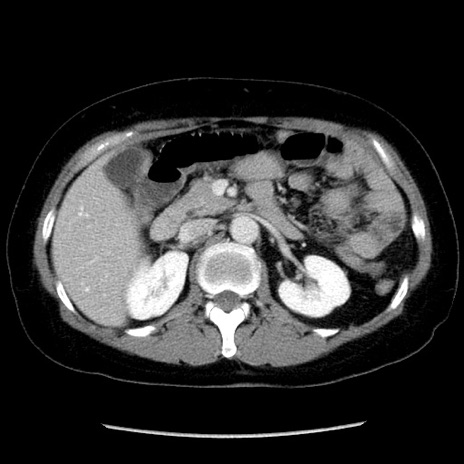

症例6(横断像)

【症例】50歳代女性

【主訴】下腹部痛

【現病歴】本日朝より下痢2回あり。 昼食を食べた後、嘔吐3回、下腹部痛認め、症状軽快せず、当院救急搬送。

最終食事:本日昼(生ものなし)。 昨日の夜、刺身を食ぺたとのこと。周囲に同様の症状の者なし。普段、排便は毎日あるとのこと。

【既往歴】卵巣癌術後(8年前に当院で卵巣摘出)

【身体所見】 意識清明、腹部:平坦、腸蠕動音→、やや硬、下腹部自発痛・圧痛あり、反跳痛あり、筋性防御なし。

【データ】WBC 16000、CRP 0.01